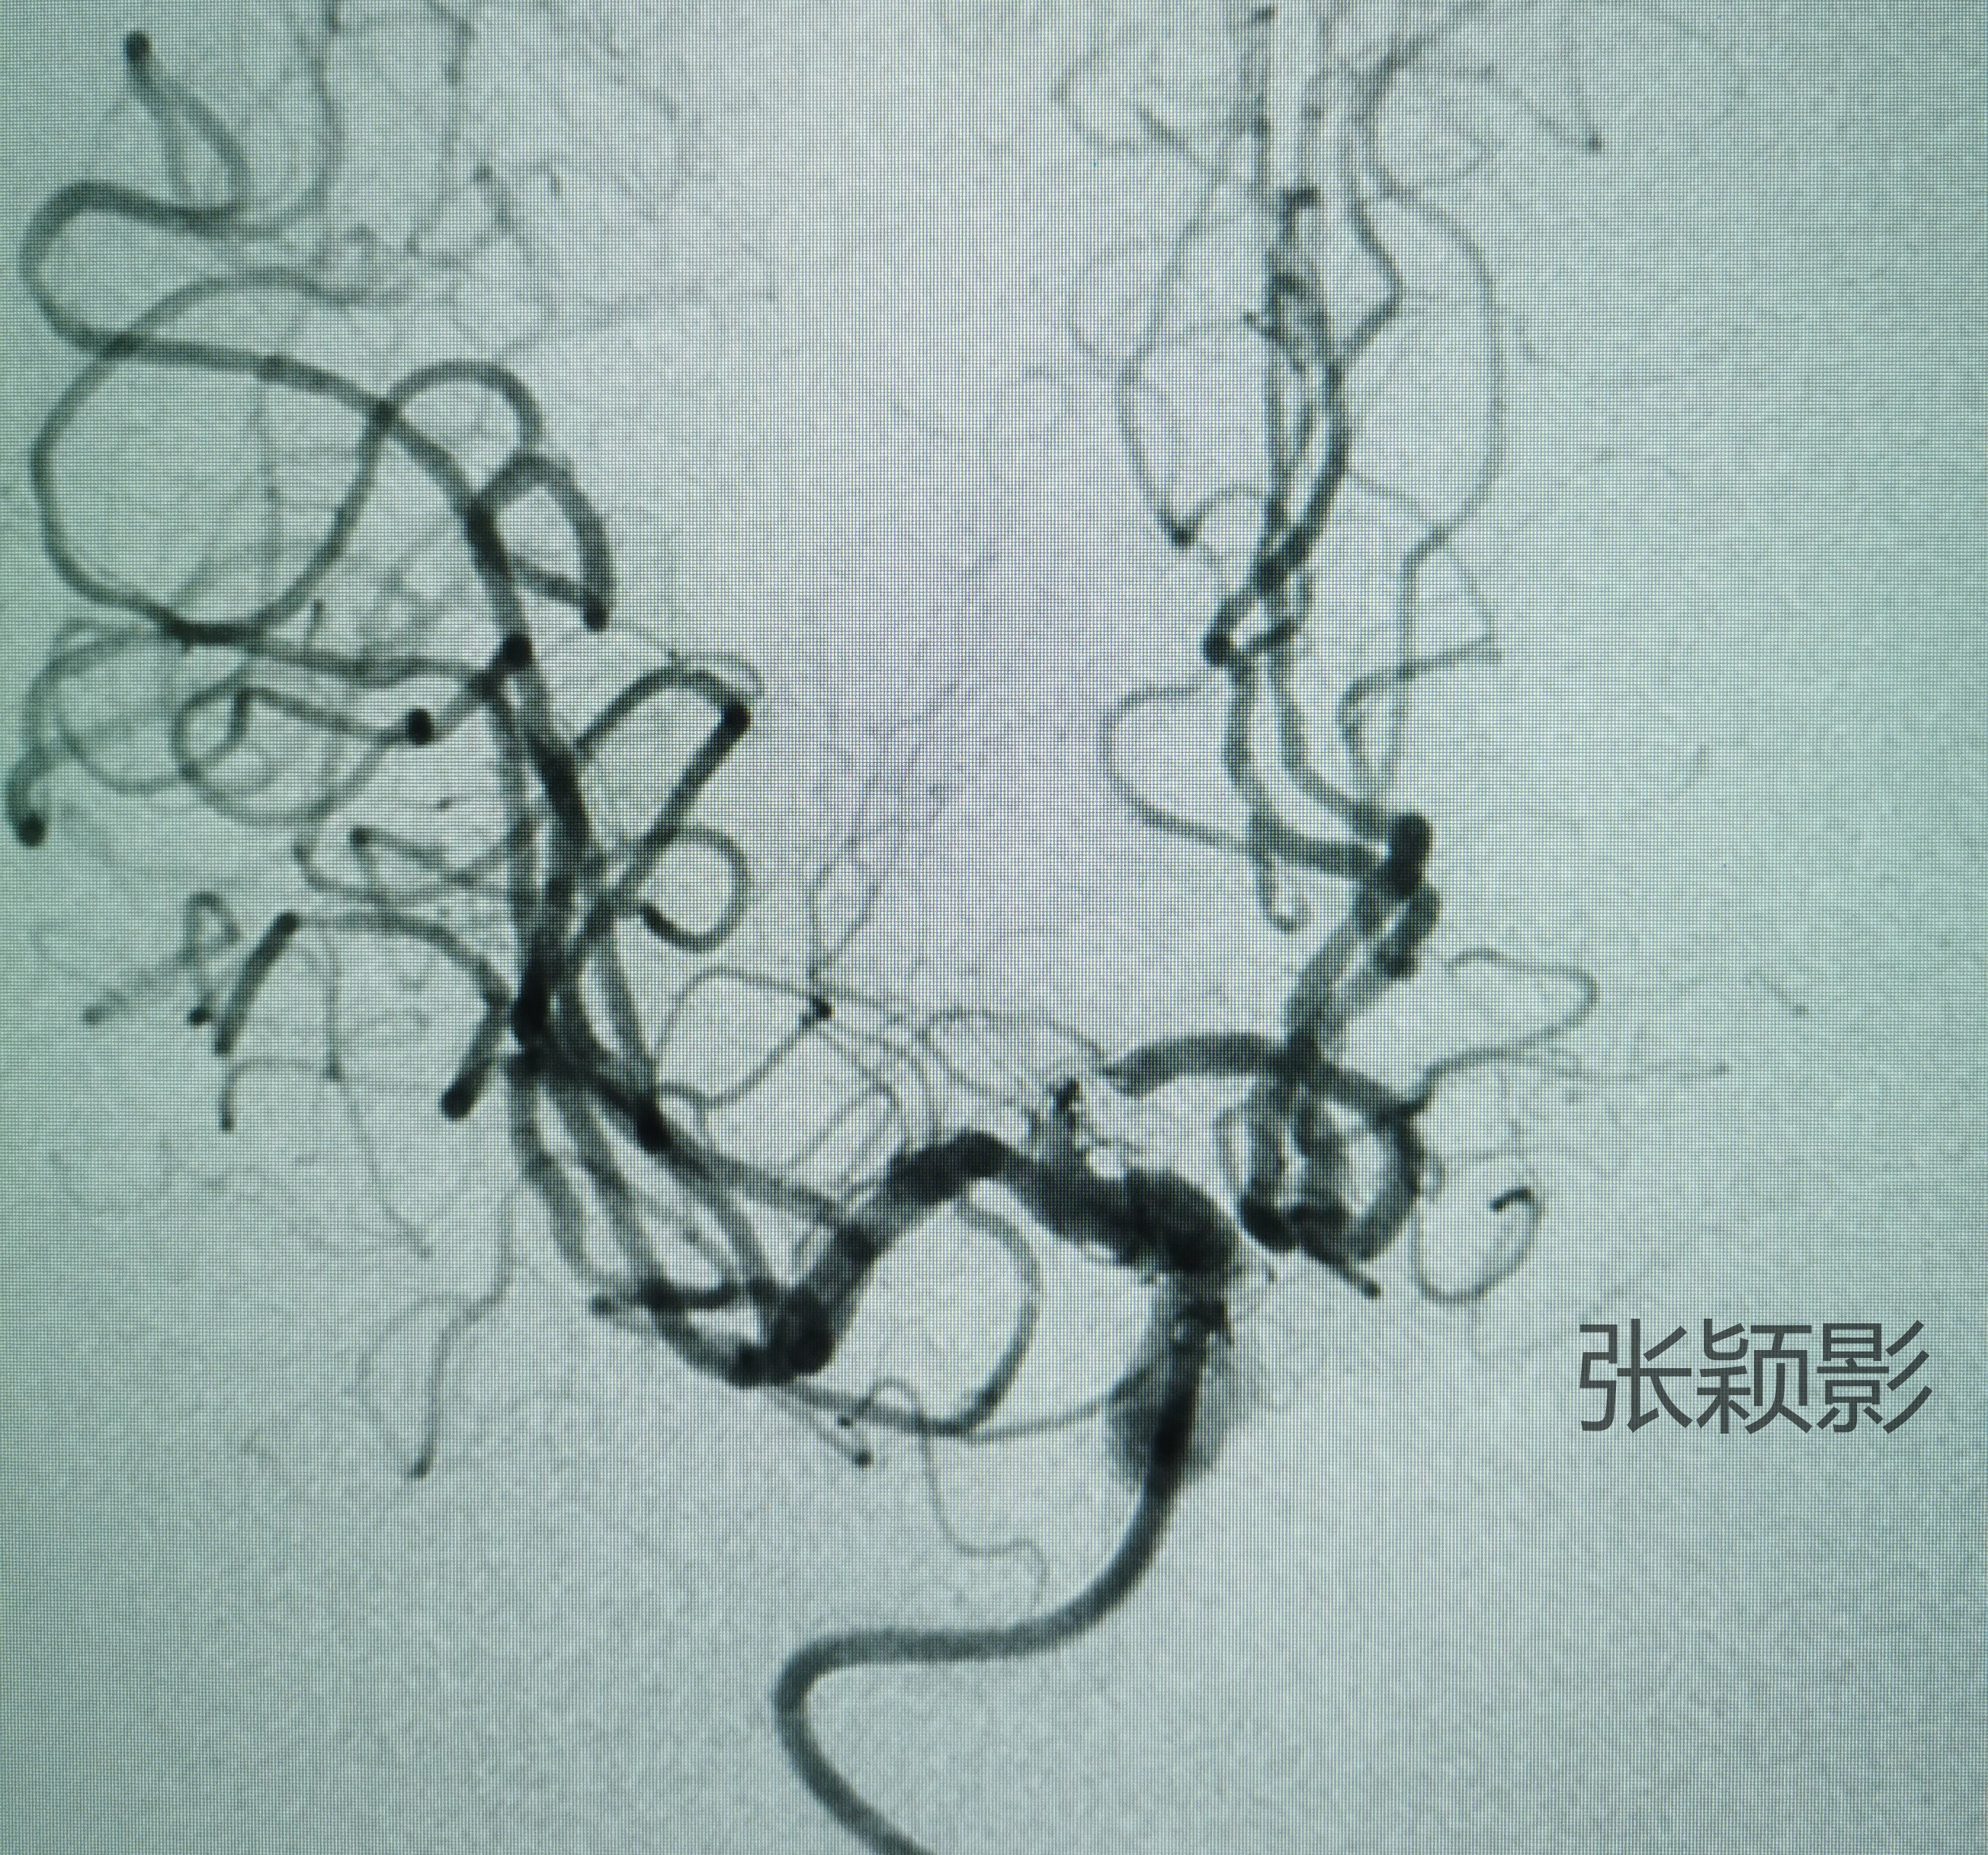

动脉瘤体通过弹簧圈栓塞保护住了,载瘤动脉血流也没有受影响。患者82岁了,双抗还是能免则免吧,撤出两根微导管,结束手术。

动脉瘤危险解除,载瘤动脉内血流通畅,患者不需要复杂的围术期用药,心情甚好😁✌